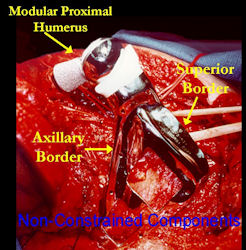

Examples of radical limb sparing surgeries for osteosarcomas in various anatomic locations (distal femur, proximal tibia, proximal humerus, scapula)

In each case, the tumor and bone from which it arose were resected. This required meticulous dissection, mobilization and preservation of adjacent pertinent neurovascular structures. In each case presented here, the defect was reconstructed with a special modular segmental tumor prosthesis. This also replaces the adjacent joint in many instances.

Proximal Humerus: Radical Limb Sparing Extra-Articular Resection and Prosethetic Reconstruction